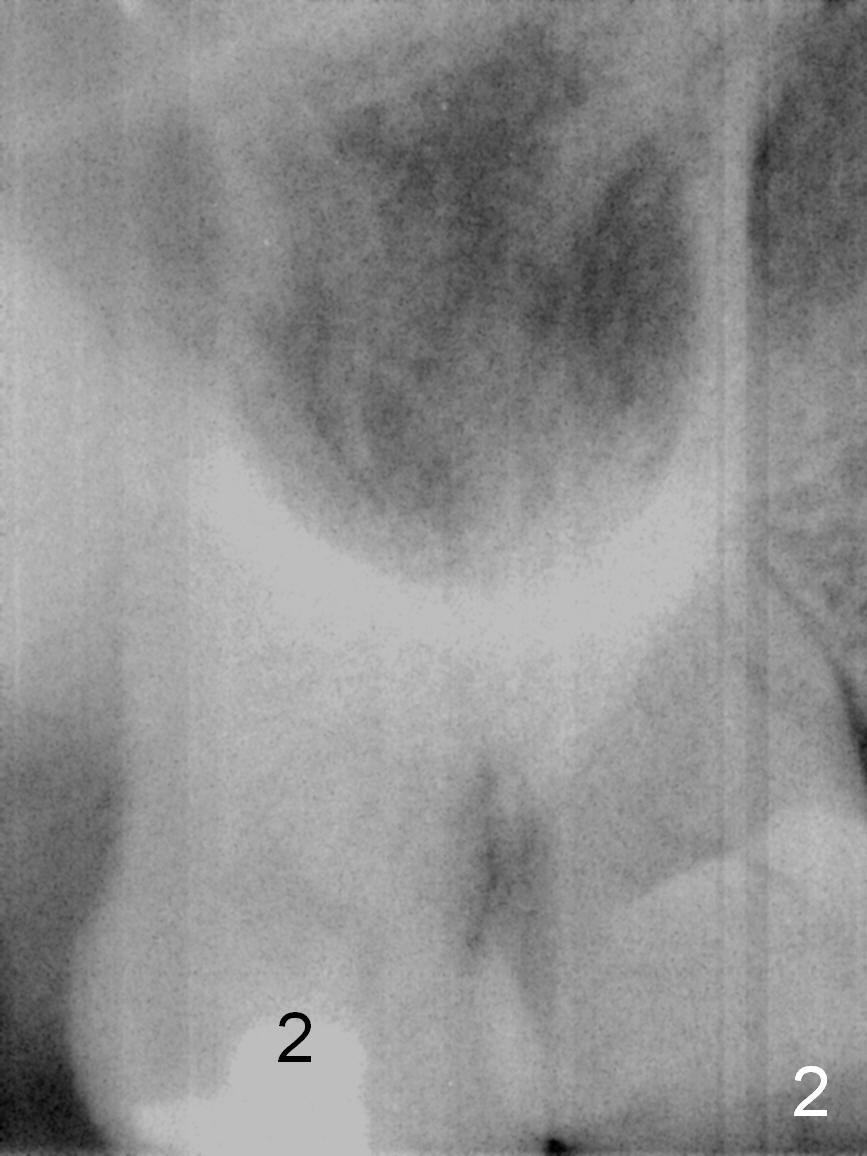

A 54-year-old woman has nocturnal pain at the tooth #2 (Fig.2), one year after extraction of the tooth #14 (Fig.1).  A mesiodistal crack line is found at root canal therapy (Fig.3 arrowheads).  The tooth appears to be nonsalvageable.  The socket is either single or 3.  Cut and soak 3 large pieces of gauze in Metronidazole.  When the tooth is extracted, we will decide whether the gauze needs to be cut further.  Depending upon the size of the septum, a relatively small (4.5x9 mm Fig.4) or large (6.5 mm) implant will be placed.  The largest pair abutment will be installed to close the socket.